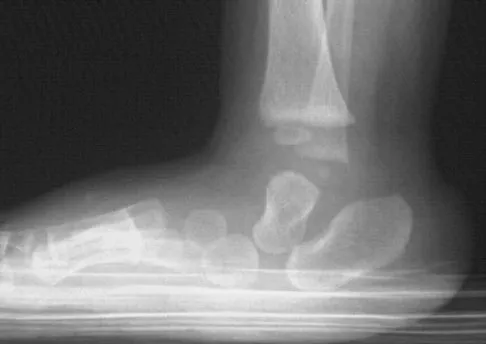

Figures 33a and 33b show the radiographs of a 10-year-old girl who reports a 4-month history of medial foot pain after she was kicked while playing soccer. The pain is worse with activity and partially relieved by rest. Examination reveals tenderness directly over a prominent navicular tuberosity. Management should consist of

Explanation

An accessory tarsal navicular is located at the medial tuberosity of the navicular bone. Nearly all children and adolescents who have a symptomatic accessory tarsal navicular bone become asymptomatic when they reach skeletal maturity. Initial management should include activity restrictions, shoe modification to avoid pressure over the prominent navicular, and non-narcotic analgesics. Although anecdotal, the use of arch supports may be helpful. When pain is refractory to these methods, a short period of cast immobilization may be useful. Surgery should be reserved for patients who have disabling symptoms despite a prolonged period of nonsurgical management. When surgery is indicated, simple excision of the accessory navicular is recommended. Sella EJ, Lawson JP, Ogden JA: The accessory navicular synchondrosis. Clin Orthop 1986;209:280-285.